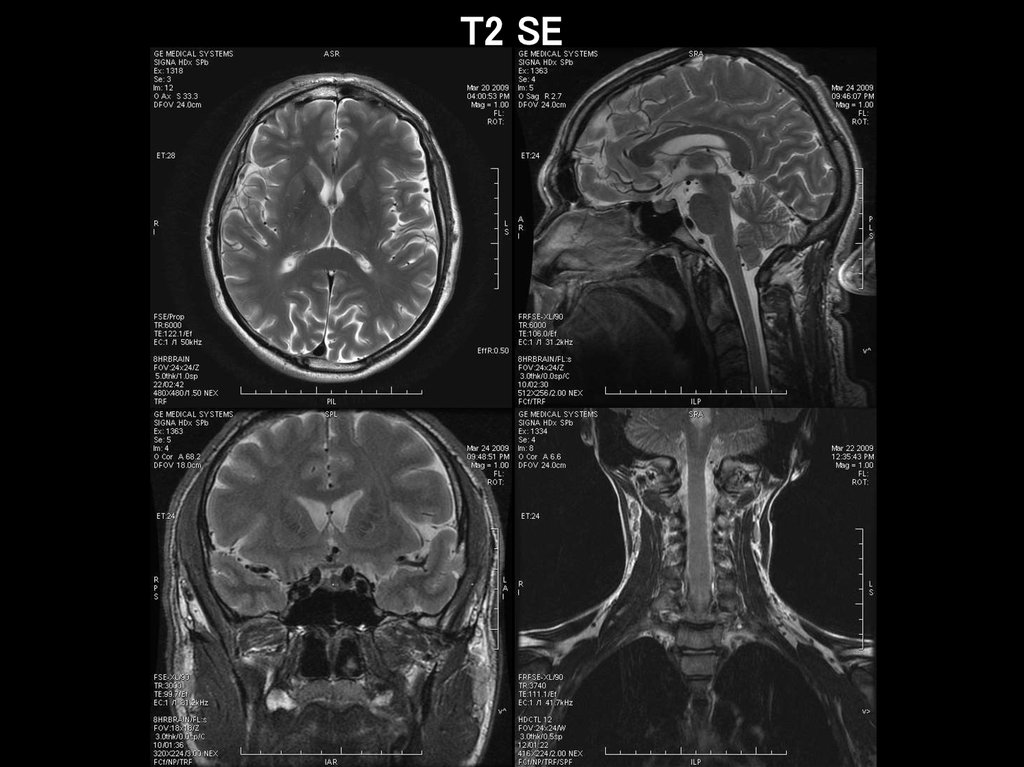

T2 SE

27.

28.